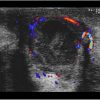

Apxe vú

Apxe vú - Ảnh 2

» Thông tin: Nữ giới – 21 tuổi.

» Lâm sàng: Sưng đau tuyến vú.